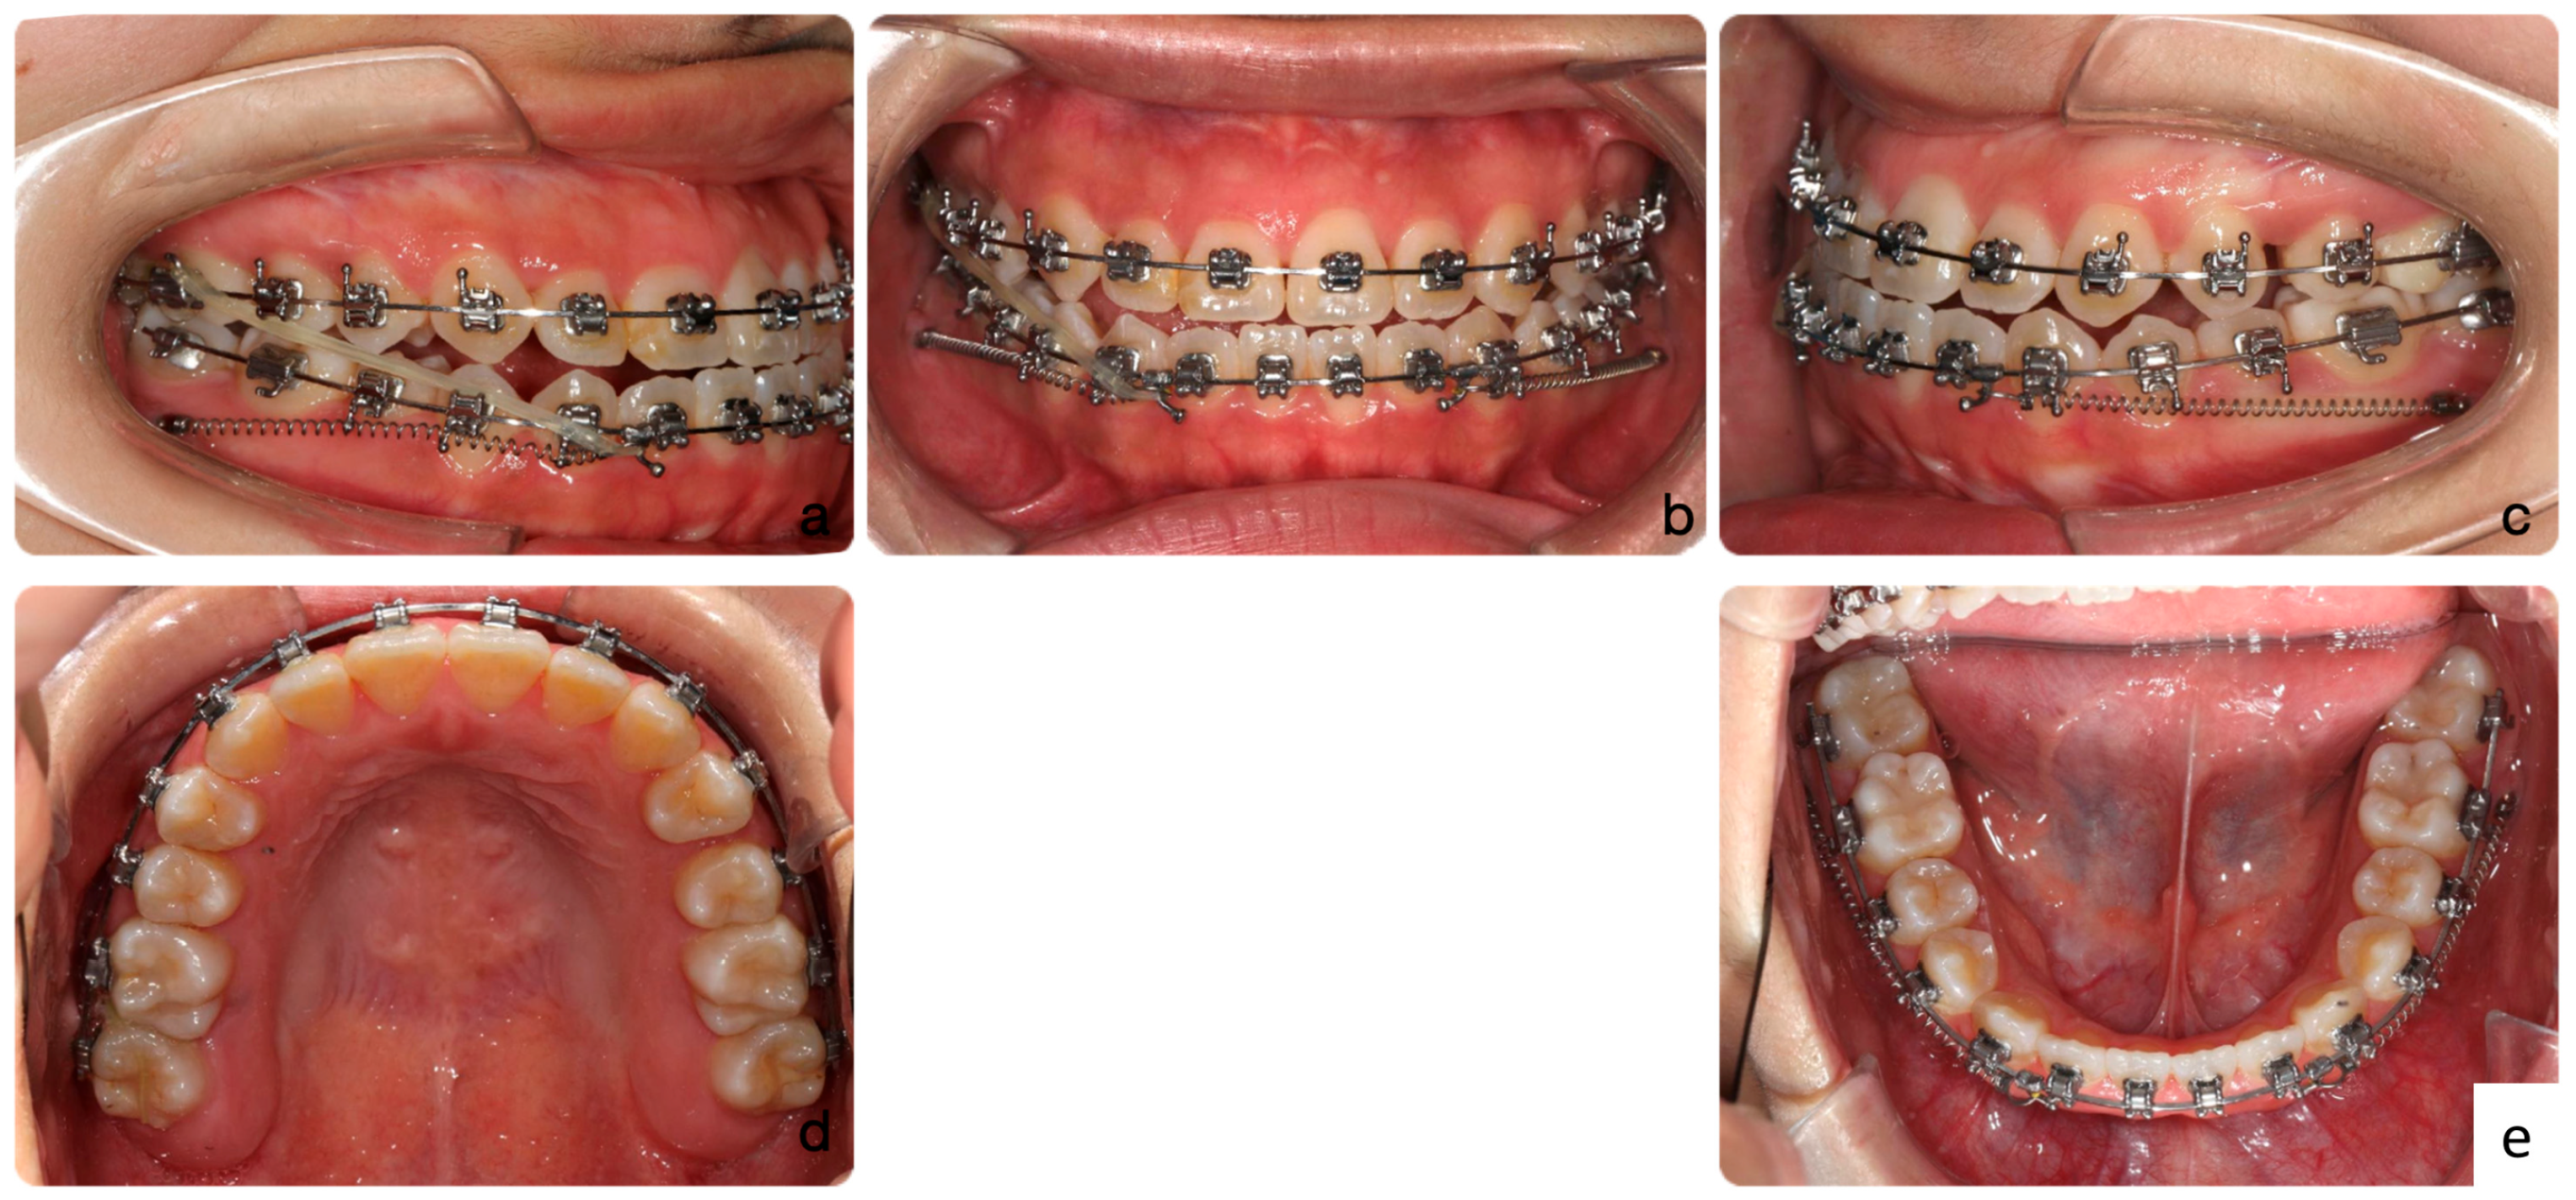

2.5. Treatment Results

| SNA | 81° ± 3° | 81° | 81.5° | 81° |

| SNB | 78° ± 3° | 83.5° | 81.5° | 81.5° |

| ANB | 3° ± 2° | −2.5° | 0° | −0.5° |

| Maxillary inclination (S-N/ANS-PNS) | 8° ± 3° | 8° | 8° | 8° |

| MMPA | 27° ± 3° | 28° | 31° | 30° |

| LFH % | 55% ± 2% | 58.5% | 58.7% | 58.6% |

| Upper incisor to Max. plane | 108° ± 6° | 126.5° | 126.5° | 126° |

| Lower incisor to Mand. Plane | 93° ± 6° | 94° | 92° | 83° |

| Lower incisor to A-Po line | 1 ± 1 mm | +12.5 mm | +8 mm | +5 mm |

| Inter-incisal angle | 133° ± 10° | 111° | 110° | 120° |

| Upper lip-E line | −2 ± 2 mm | −3 mm | −2 mm | −3 mm |

| Lower lip-E line | 0 ± 2 mm | +4 mm | +3 mm | −1 mm |